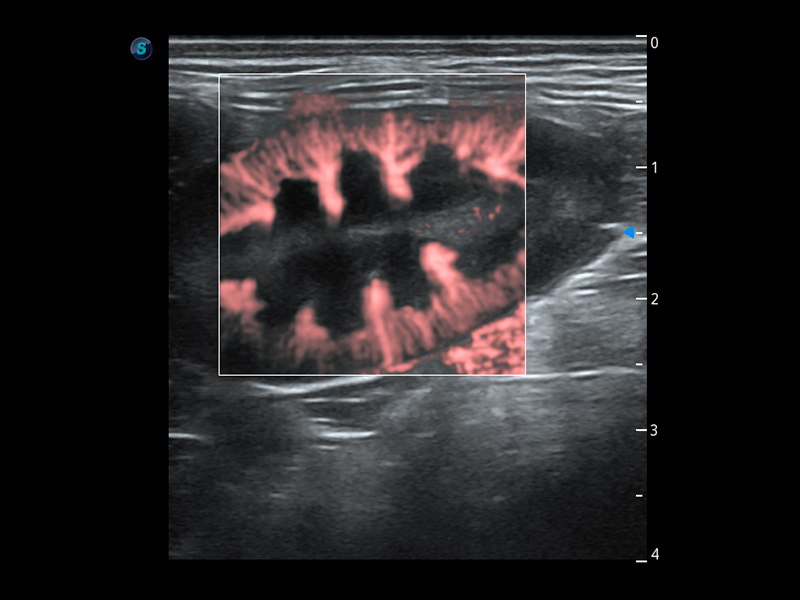

ProPet 60 作为一款高端台式动物超声设备,为动物医生的日常诊断提供了一系列贴合动物临床需求、解决临床实际问题的高级成像功能。凭借全系列高清探头,满足医生对腹部、心脏、生殖、浅表、肌骨等成像的所有需求,切实帮助您提升检查效率,提高诊断信心。

ProPet 60 尊享版

兽用彩色多普勒超声诊断系统